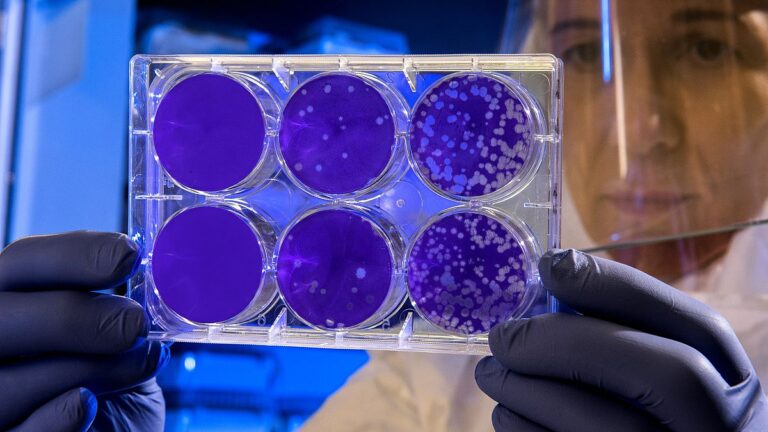

Musluk suyu ve gıdalardaki ‘kimyasallar’ kanserin yayılmasına neden olabilir | Araştırma

Sanofi, Care4Rare programının ilk adımı olan “İhtiyaç Belirleme Çalıştayı” gerçekleşti – TEKNOLOJİ